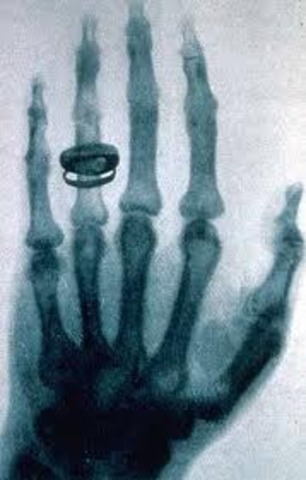

• Rayos x

Rayos x

En 1901 Wilhelm Konrad Rontgen, descubrió los rayos x.